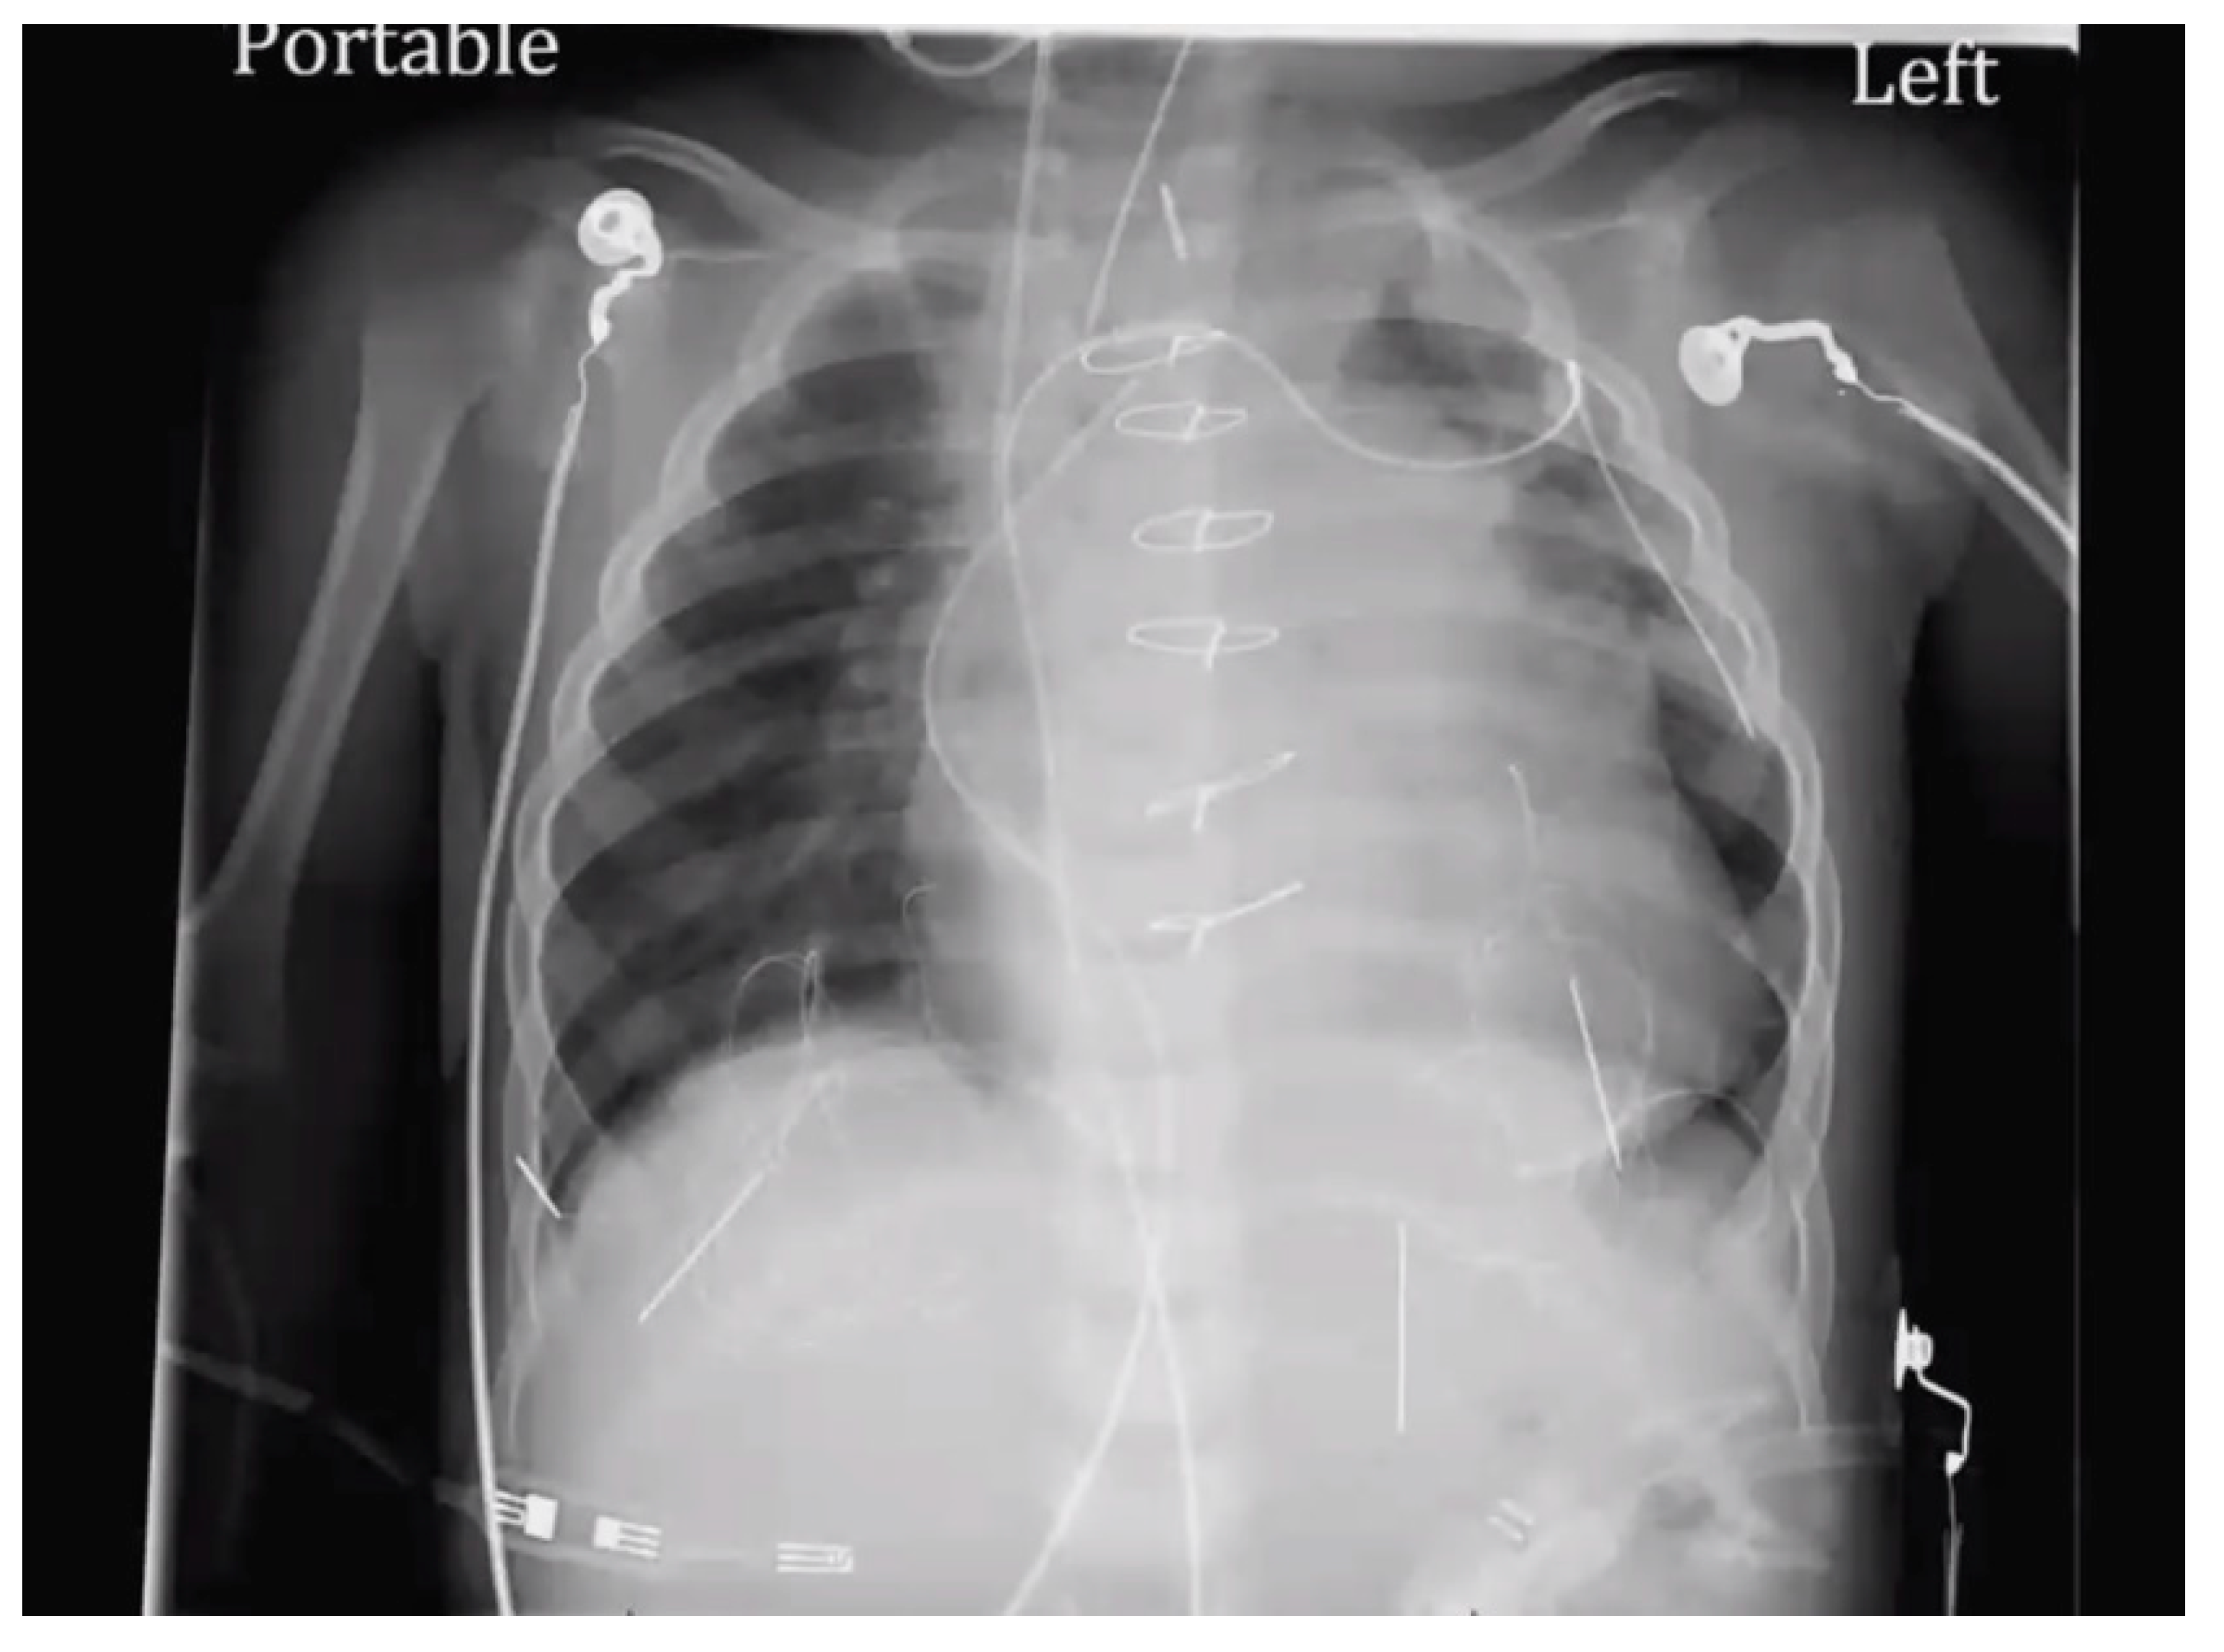

At age 17 years, she presented to the cardiology clinic for worsening cyanosis (SpO2 in 60%), erythrocytosis (hematocrit 72%), easy fatigability, and decreased exercise tolerance (NYHA Class III). Her weight 47.9 Kg, height 150 cm, and body mass index (BMI) was 21.59 kg/m². She had clubbing of fingers and toes, but no edema. Her lungs were clear to auscultation. She had normal first heart sound, single second heart sound but loud, with a faint continuous murmur on right back. There was no hepatosplenomegaly. Her electrocardiogram (ECG) showed sinus rhythm, right axis deviation, and right ventricular hypertrophy (Figure 1). Chest X-Ray showed bilateral heterogeneous vascular markings (Figure 2). Echocardiogram showed a large perimembranous VSD with aortic override and right-to-left shunt across VSD. Bi- ventricular systolic function was normal. There was mild aortic valve regurgitation. Her laboratory test was significant for a normal brain-type natriuretic peptide level of 65 pg/mL (normal, <100 pg/mL).

Figure 2. Chest X-ray (Case-1). “Boot shaped” heart and variable perfusion of the lung parenchyma.